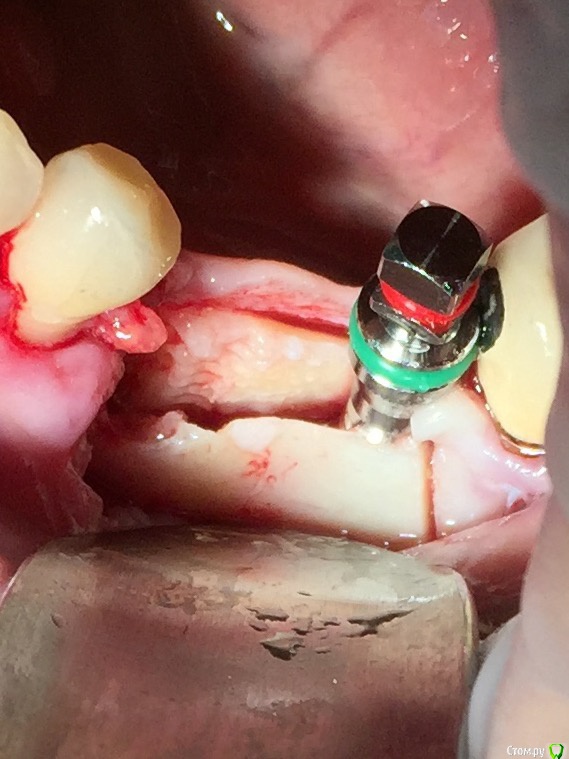

Глеб Митрофанов Опубликовано 12 сентября, 2015 Поделиться Опубликовано 12 сентября, 2015 (изменено) Решил потратить деньги , отложенные на Гамборену , приобрел набор для расщепления . Протестировал , понравилось . Особенно понравился пьезоаппарат , учитывая то , что впервые работал пьезо . За одно протестировал и джейловский гаджет для сбора кости , тоже понравился . Уже по обыкновению использовал A-PRF и I-PRF. Фото с телефона , обрезанные , на телефоне четче смотрятся. Изменено 12 сентября, 2015 пользователем Глеб Митрофанов 4 Ссылка на комментарий

АлинаК Опубликовано 17 сентября, 2015 Поделиться Опубликовано 17 сентября, 2015 Решил потратить деньги , отложенные на Гамборену , приобрел набор для расщепления . Протестировал , понравилось . Особенно понравился пьезоаппарат , учитывая то , что впервые работал пьезо . За одно протестировал и джейловский гаджет для сбора кости , тоже понравился . Уже по обыкновению использовал A-PRF и I-PRF. Фото с телефона , обрезанные , на телефоне четче смотрятся.Добрый день! Подскажите,пожалуйста,название набора и производителя(если можно) Ссылка на комментарий

Глеб Митрофанов Опубликовано 17 сентября, 2015 Автор Поделиться Опубликовано 17 сентября, 2015 Добрый день! Подскажите,пожалуйста,название набора и производителя(если можно) Мистер Кюрет , продает Имплант Ру Ссылка на комментарий